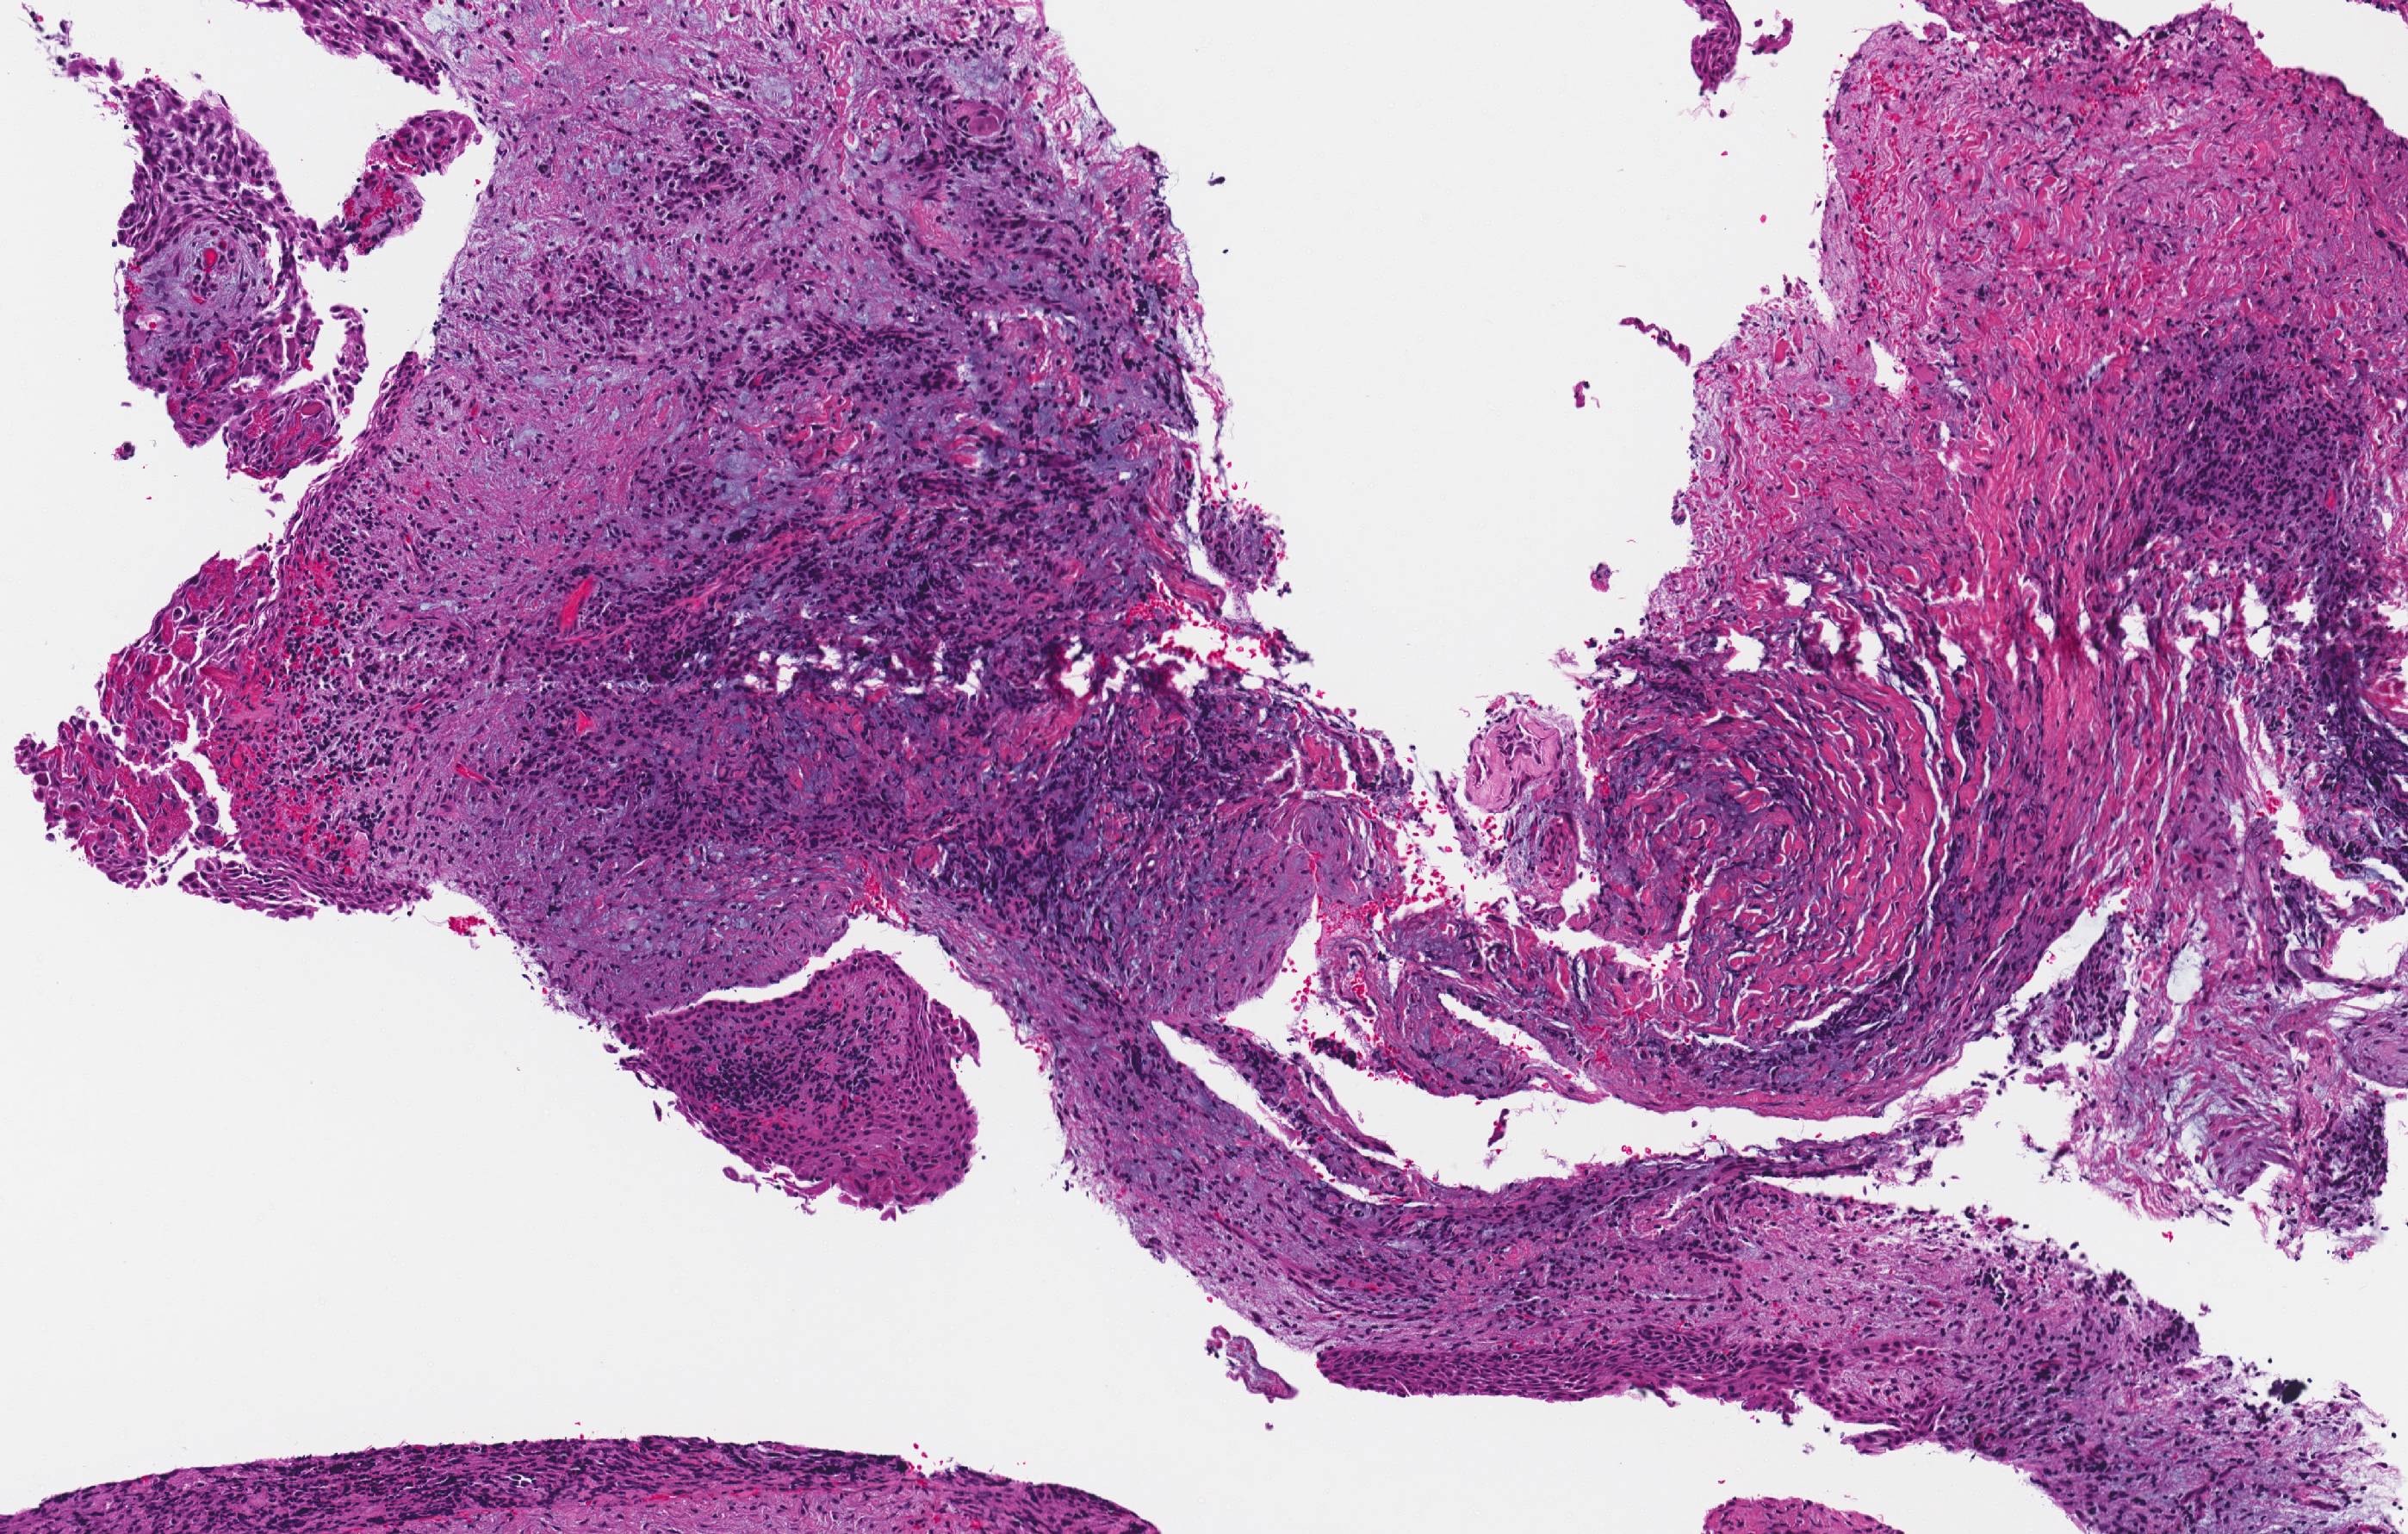

Microscopic (histologic) description

- The microscopic findings are not specific and cannot distinguish between the variants of inflammatory odontogenic cysts, or a markedly inflamed developmental dentigerous cyst

- Clinical and radiographic correlation essential

- Connective tissue wall

- Heavy mononuclear inflammatory cell infiltrate

- Hyperplastic nonkeratinizing stratified squamous epithelium

- Often with hemosiderin pigment or cholesterol clefts